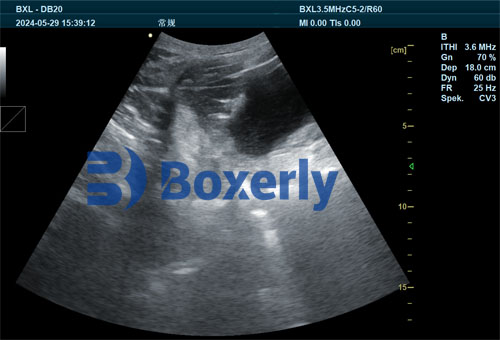

The success of ultrasound relies on its ability to visualize internal structures using high-frequency sound waves, typically between 1.5 to 18 MHz. When these waves are transmitted into the sow’s body via a transducer, echoes are reflected differently depending on tissue density. The ultrasound machine converts these echoes into real-time images, allowing us to interpret the condition of soft tissues such as the uterus and ovaries.

In reproductive monitoring, B-mode (brightness mode) scanning is the most commonly used format. It provides a two-dimensional grayscale image that helps us assess the morphology of reproductive organs. In practice, we apply ultrasound gel to ensure acoustic coupling between the transducer and the animal’s skin, enabling clearer imaging.

Because the reproductive organs are located deep within the abdominal cavity, using the appropriate probe frequency is essential. Lower frequencies penetrate deeper, making them suitable for scanning large animals like sows, though with some trade-off in image resolution. In contrast, higher frequencies give better resolution but shallower penetration.